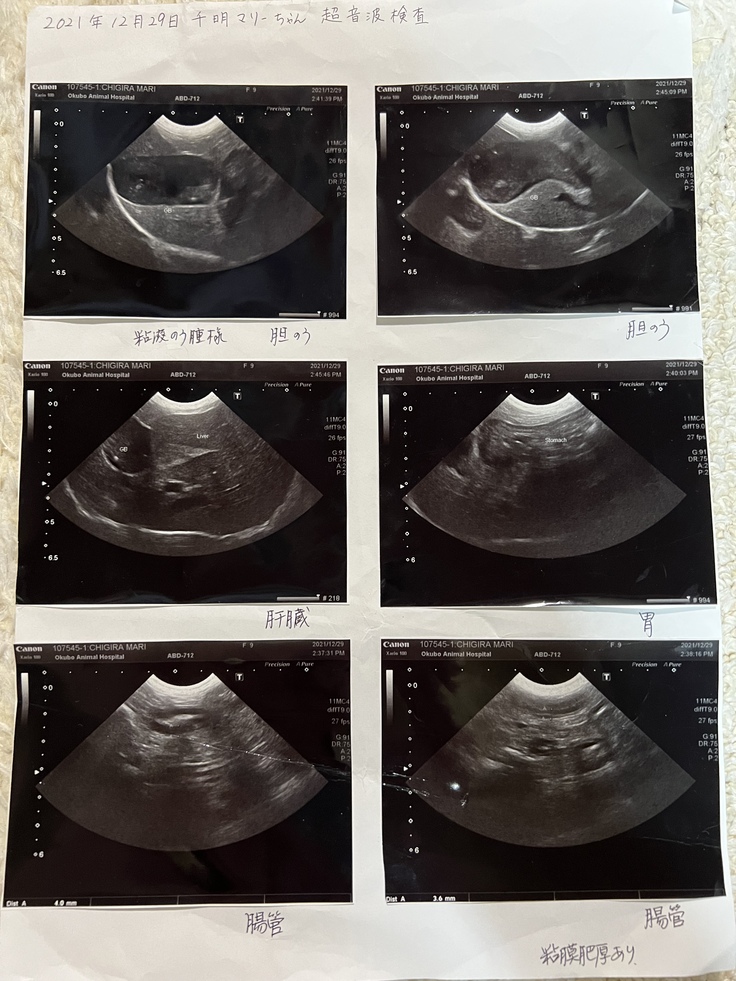

超音波検査も含め、詳しく調べてもらう事に。

白血球が異常に多く、低アルブミン血漿、貧血、超音波検査では腸管には粘膜肥厚が見られました。胆嚢粘液嚢腫?胆嚢の中に胆石もあるけど、ゼリーとかキウイみたいのがあるらしいです。まだ余力はあるがやはり手術はしないといけないそうです。

超音波検査や血液検査、全てやってもらう事に。